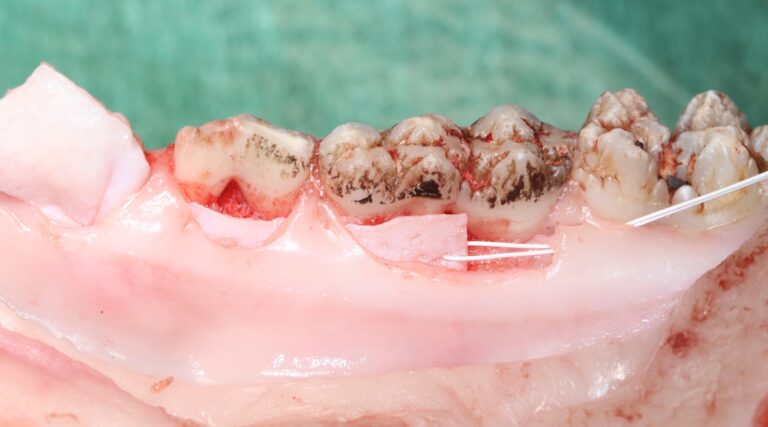

Der Schwerpunkt liegt auf dem praktischen Erlernen der entsprechenden chirurgischen Techniken am Schweinekiefer.

Hands-on-Übungen am Schweinekiefer

- Nahttechniken

- Rezessionsdeckung in modifizierter Tunneltechnik

mit azellulärer porziner dermaler Matrix (Novomatrix, Firma Camlog) - Entnahme eines Bindegewebstransplantats in der „Single-Incision“ Technik

- Entnahme eines Bindegewebstransplantats als deepithelisiertes FST

- Koronaler Verschiebelappen mit BGT mit und ohne vertikale Inzisionen